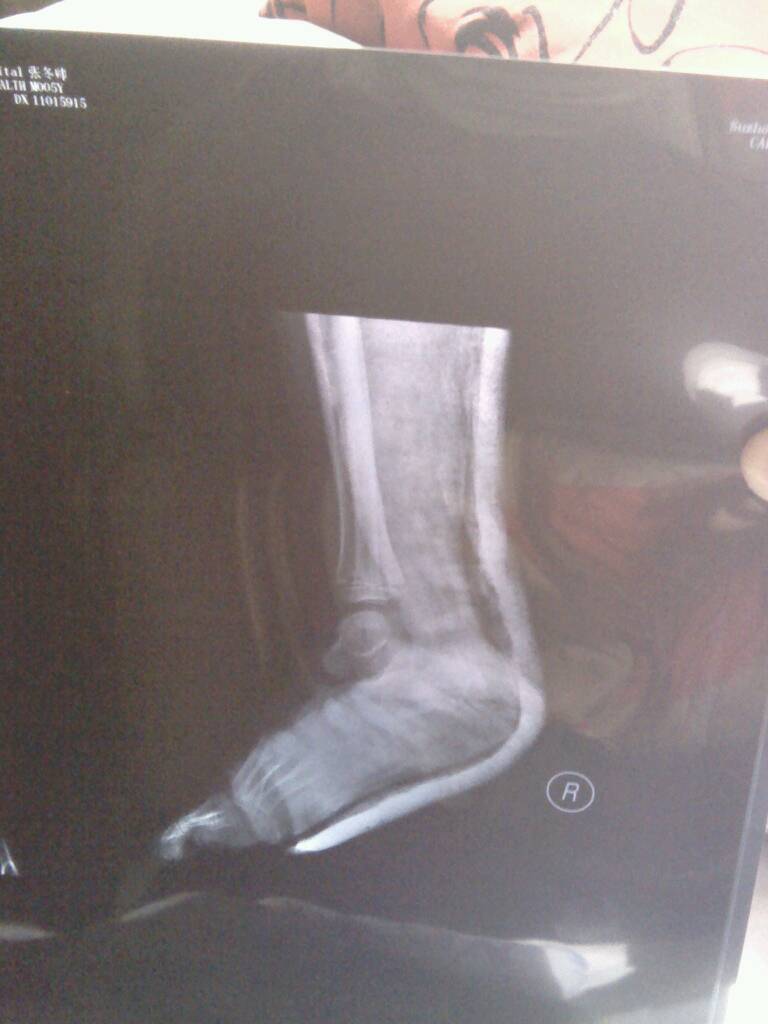

你好,我家小孩五岁脚后骨骨折已有十几天,现在也不肿不疼了,他在床上总是动来动去的,会不会错位?请帮 你好,我家小孩五岁脚后骨骨折已有十几天,现在也不肿不疼了,他在床上总是动来动去的,会不会错位?请帮忙看下x片,一个星期复查拍的,因为担心辐射,不敢频繁拍。 点击展开 匿名用户 2014-03-07 12:49 为您推荐: 其他回答 病情分析: 您好,这样的话,需要结合治疗方式的. 指导意见: 通常如果是通过石膏固定,并且没有着重下地的话,则通常不会,需要继续卧床休息,疗养的/ 匿名用户 2014-03-07 12:54 相关问题 你好我家小孩五岁脚后骨骨折已有十几天,现在消肿也不疼了,老在床上动来动去,会不会错位啊,请专家帮忙 2,3岁的小孩,股骨骨折、错位急 宝宝脚胫腓骨骨折三个月了没有打石膏但是没有错位以后会有什么影响